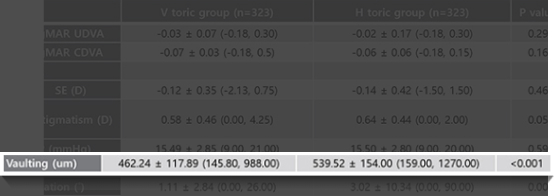

'렌즈삽입술의 회전 안전성을 위한 수직 삽입의 임상 결과와

비교 연구'를 통해 회전의 안정성이 더 우수함을 입증하고

상대적으로 더 낮은 볼팅으로 우수한 시력교정

결과를 보여 기존의 수평 삽입을 대체할 수 있는 방법으로

평가되었습니다.

Low 볼팅에서도

낮은 렌즈 회전 가능성

렌즈회전 방지를 위해 high 볼팅의 관례이나, V-토릭 ICL은

렌즈회전 방지를 위해 high 볼팅의 관례이나, V-토릭 ICL은

Low 볼팅에도 낮은 렌즈 회전 가능성을 보이며,

볼팅을 높여서 발생하는 부작용을 예방할 수 있다.